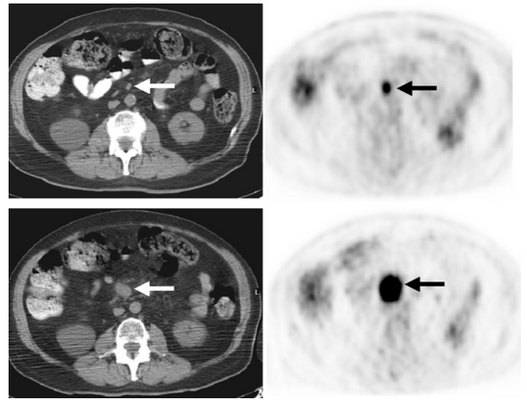

Снимки спустя 4 месяца после первого исследования. Накопление 18f-FDG 1,2х1,5 см мезентериального лимфатического узла (указано стрелками). На последних двух изображениях узел также гиперметаболический размером 3,8х4,0 см с накоплением 18f-FDG, что характерно для лимфом